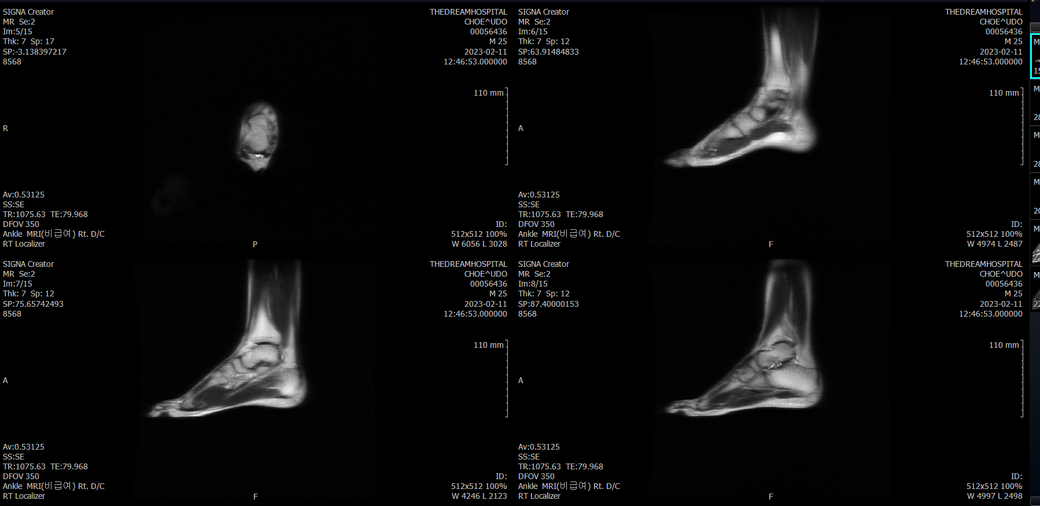

오른발목 mri 전체사진입니다. 제가 병원을 갈수없는상황인지라.... 봐주시면 감사하겠습니다.

엑스레이에서는 문제가 없다고 하여 오른발목 mri촬영했습니다.